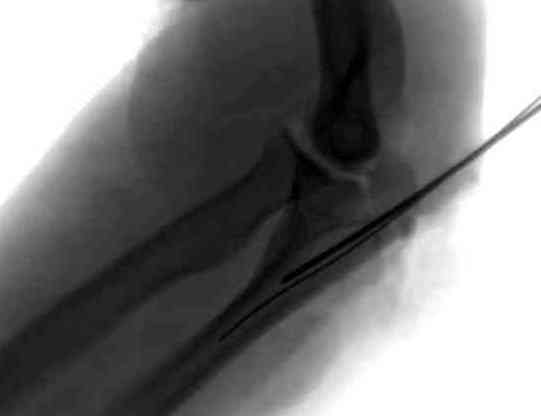

Техника Weber или Tension Wire Technique, все нансы описаны на лекции James Goulet на сайте Basic Fracture Course http://www.hwbf.org/ota/bfc/goulet/exp.htm

из-за многооскольчатости неприемлемы для данного

случая.

Несмотря на дешевизну, всего две спицы и проволока, создается хорошая компрессия, но имеются множественные случаи ранней миграции спиц.